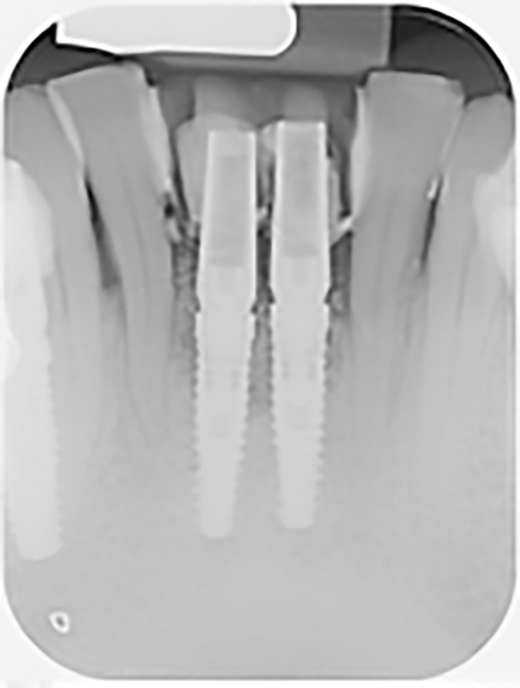

Si effettua un esame radiografico di secondo livello per procedere con la progettazione tridimensionale degli impianti in sede 3.1 e 4.1 (figure 5-6).

Si effettua la chirurgia implanto protesica guidata con mascherina (figura 8), si posizionano gli impianti 3.25 x 13 mm con un torque di 25 N (figura 9), si inseriscono i pilastri definitivi e si sutura (figura 10). Lo stesso giorno vengono ribasati e consegnati i provvisori solidarizzandoli con composito agli elementi 32-42 (figura 11).

Si effettua una radiografia di controllo dopo il posizionamento degli impianti e dei provvisori (figura 12).

In seguito all’estrazione degli elementi 3.1 e 4.1 si osserva a una settimana di follow up la perfetta guarigione dei siti (figure 4-5). I successivi follow up mostrano come la rigenerativa abbia ristabilito gli adeguati volumi ossei e grazie all’analisi tridimensionale dei siti implantari è possibile pianificare correttamente il posizionamento degli impianti (figura 6).

Dalle radiografie (figure 1a, 3 e 11) si nota come ci sia stato un incremento del tessuto osseo.